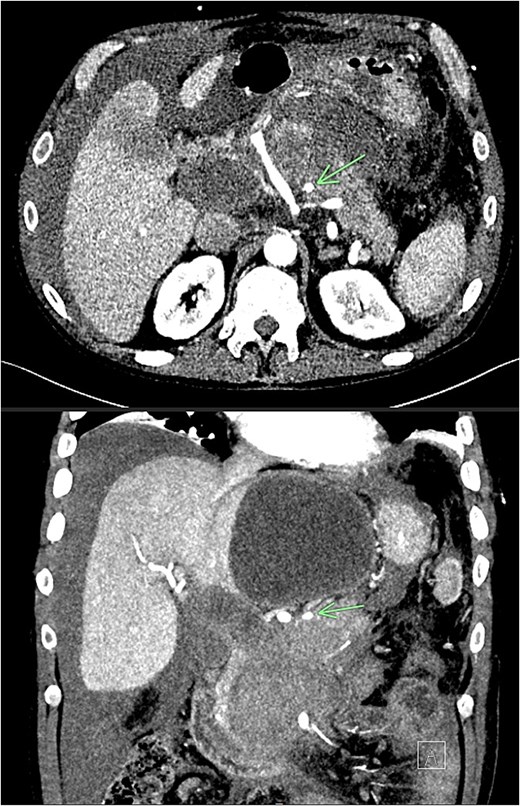

Despite the absence of abdominal symptoms, a computed tomography of the abdomen and pelvis (CTAP) was performed due to markedly elevated lipase levels. The CTAP (Figs 3–5) revealed evidence of acute pancreatitis (Fig. 5, arrow), with a complex peripancreatic fluid collection (Fig. 3, arrow). Additionally, a focal thrombus was observed within the portal venous confluence (Fig. 4, arrow). Further ultrasound of the gallbladder was negative for gallstones (Fig. 6), ruling out gallstone-induced pancreatitis.

CTAP coronal view; focal thrombus within the portal venous confluence (arrow).